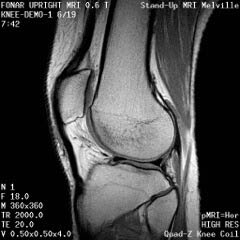

The Prostate without an Endorectal Probe |

The Heart |

![]() |

| Prostate: Delineation of Peripheral Zones (PZ), Cortical Zone (CZ) and Vescicles without an Endorectal Coil. | |

Cervical Spine |

|

Upright Neutral |

Upright Extension |

Unsuspected

Disc Herniation in Extension |

The Liver, Kidney

and Small Intestine

Bladder

and Uterus in Pelvic Floor Dysfunction (PFD) |

Lumbar Spine |

Recumbent, Weightless |

Upright, Weight-Bearing |

Figure 8.

Figure 8a-8d.

Further examples of the exceptional anatomic detail

made visible by the DISCOVERY

of Damadian of the pronounced differences in the decay

rates (relaxations) of the NMR signals

of the body's normal tissues (Figure

6). The DISCOVERED

differences supply the pixel amplitude differences

"PIXEL CONTRAST (IMAGE DETAIL)"

that produce, for the first time in medical history,

the detailed visualization of normal human anatomy

MRI is noted for. Note the visualization of the

vestibular and cochlear nerves

WITHIN

the internal auditory canel (Figure 8b) and the visualization

of the hypothalamic

tract (that transports hormones from

the brain) WITHIN

the pituitary stalk. (Figure 8c)